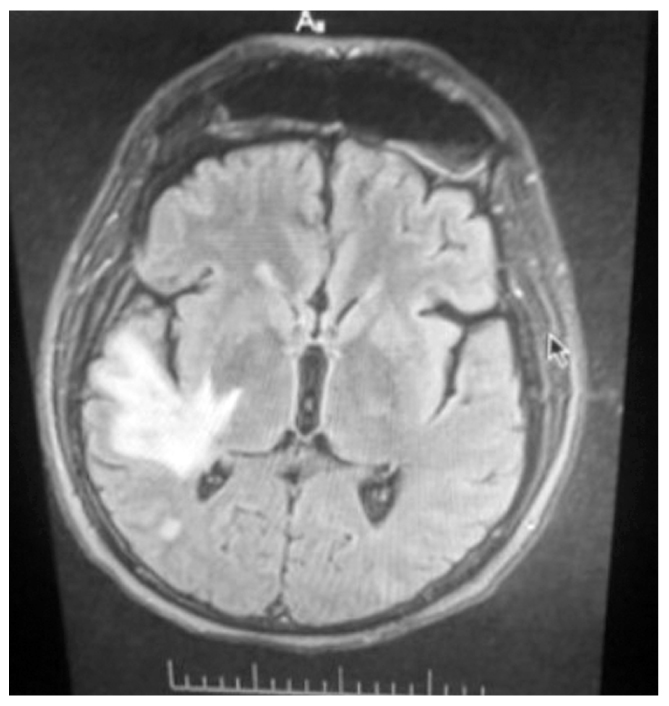

При МРТ головного мозга от 07.12.2021 выявлены крупноочаговые изменения белого вещества головного мозга правой височной доли и гигрома правой лобной доли (рис. 1).

Рис. 1. Магнитно-резонансная томография головного мозга пациента С. с энцефалитическими очагами.